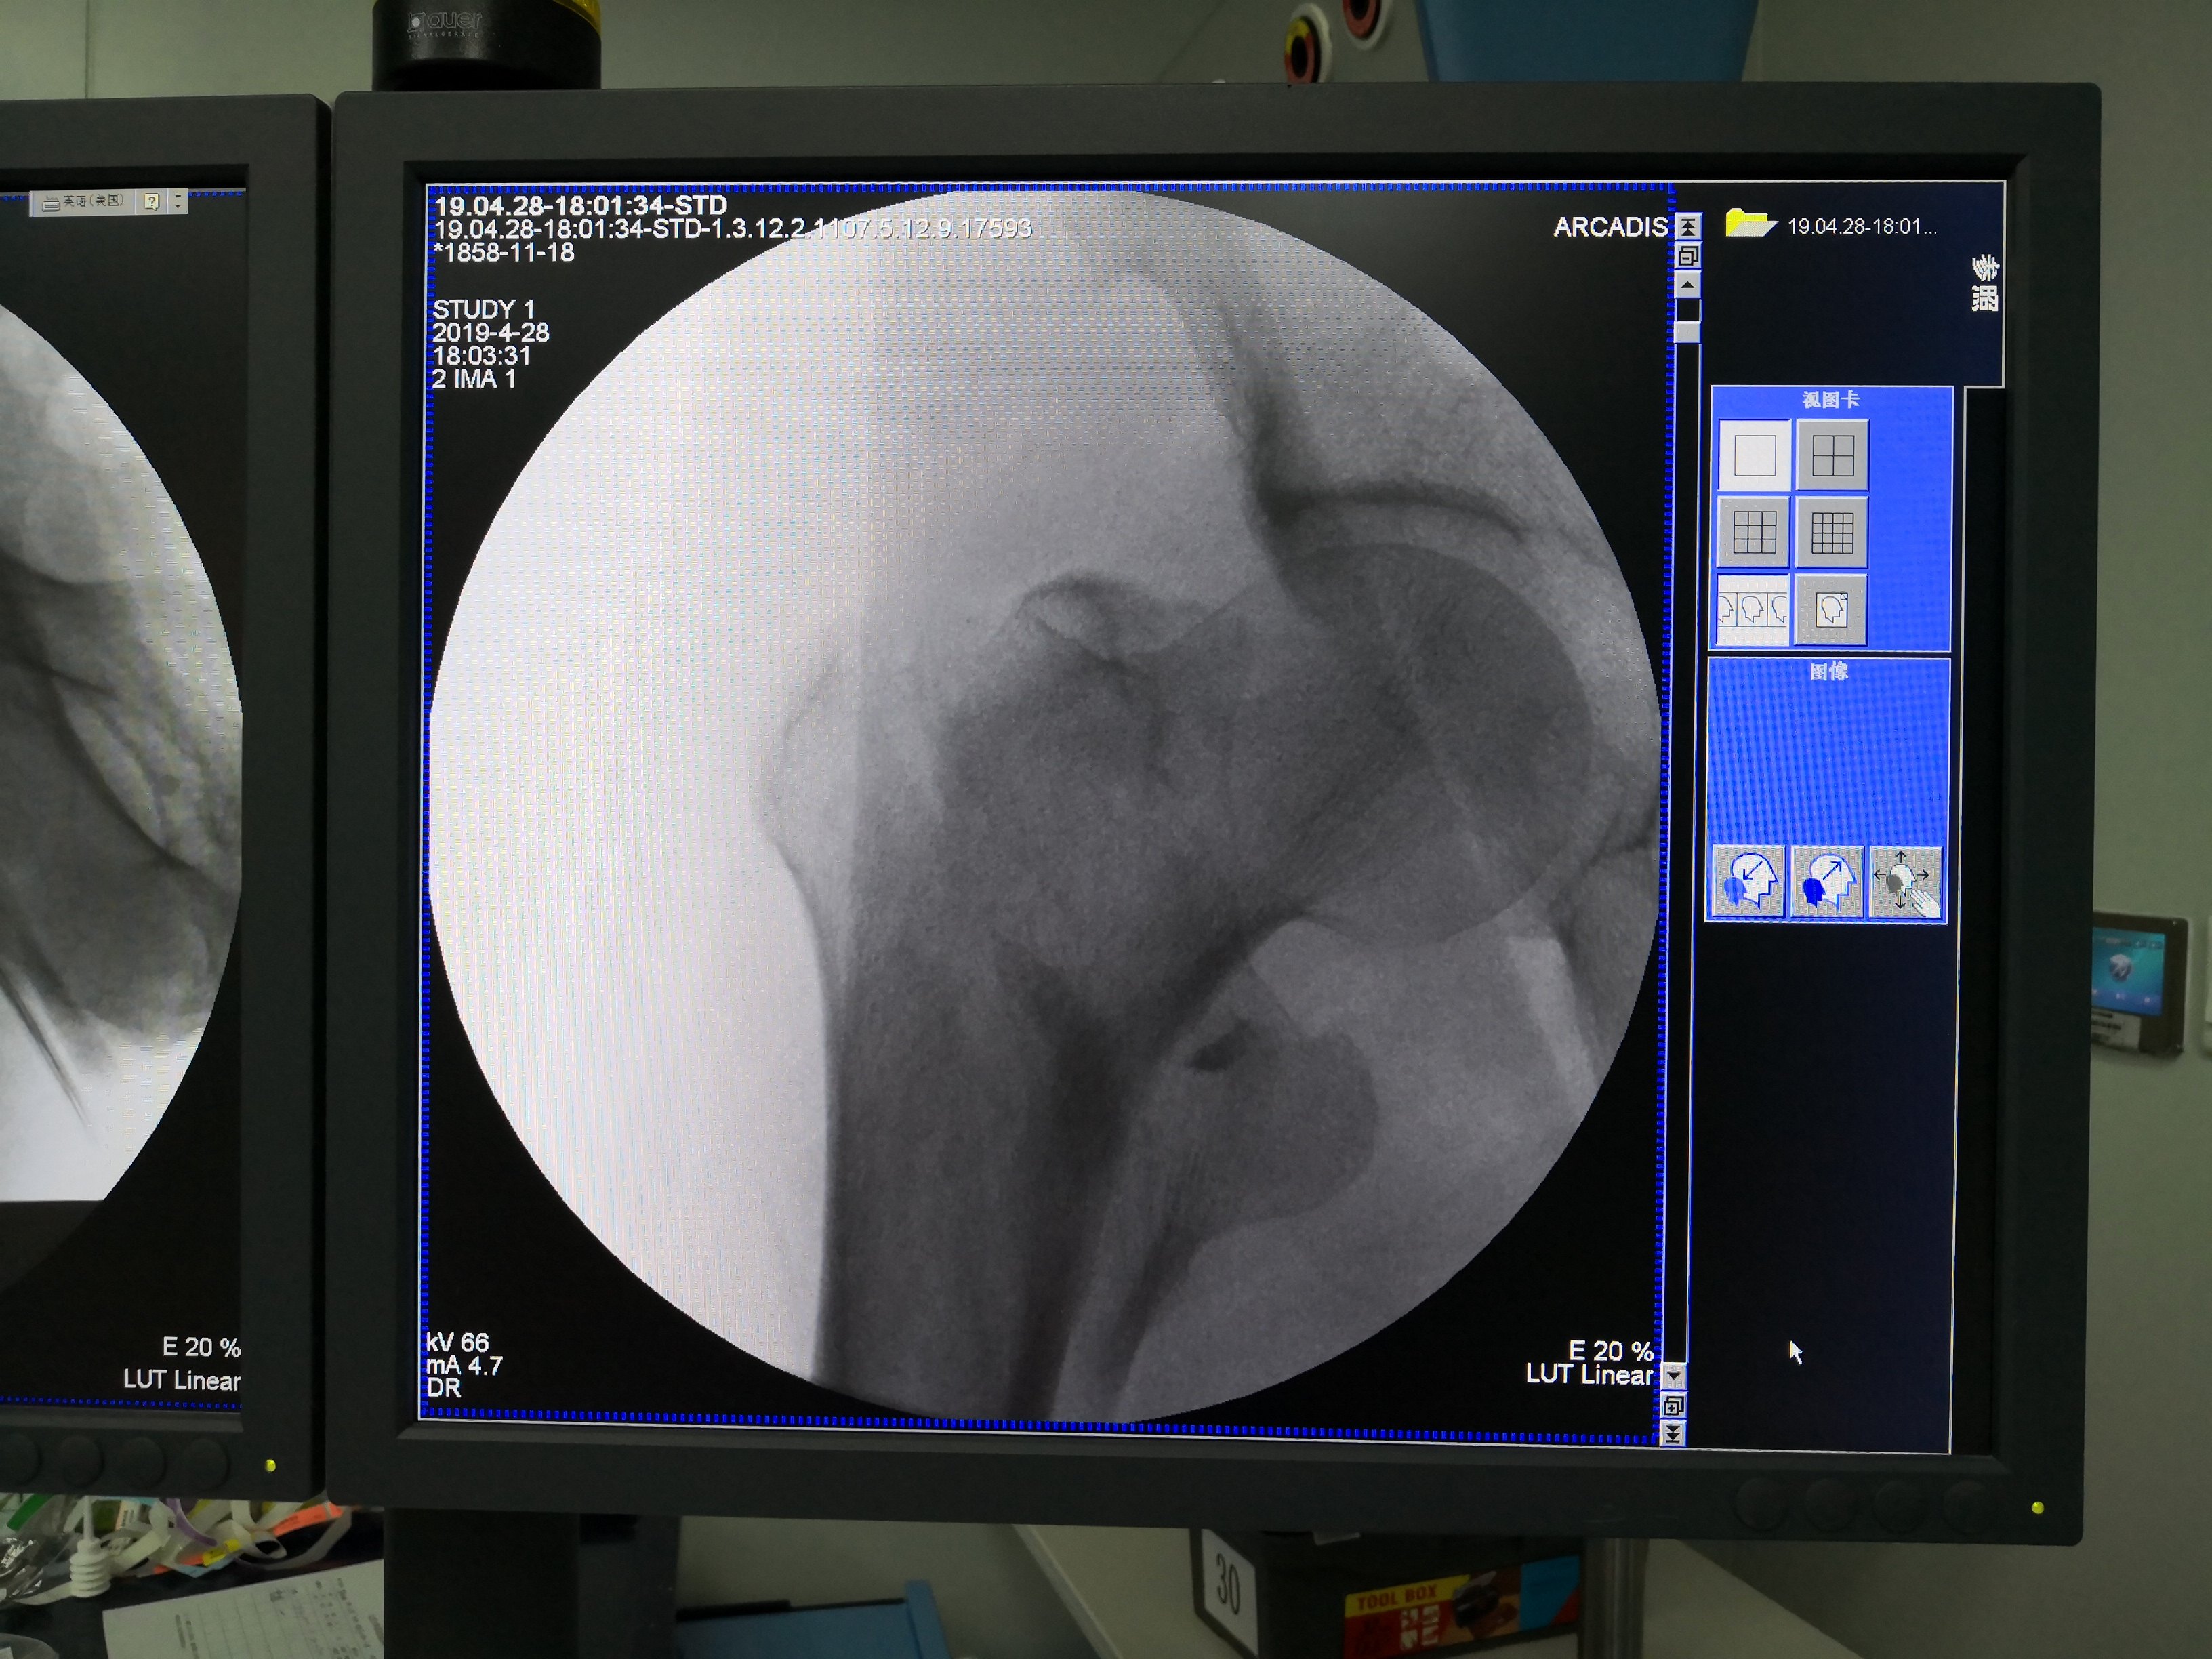

近2月收了5例股骨转子间骨折,都做了手术,手术效果都非常好。今天我们聊聊股骨转子间骨折是怎么回事。首先我们说说它的定义,股骨转子间骨折系指股骨颈基底至小转子水平以上部位所发生的骨折,为老年人常见的髋部骨折。我收这5例患者全部是摔跤所致 ,有的是在洗澡房摔的 ,有的是在厨房摔的,有的是下雨天出去买菜摔的,有的半夜起床上洗手间时摔倒的,她们有个共同的特点年龄大,有时想帮家人做点事,但力不从心,平衡能力差,加上洗澡房、厨房、下过雨的地面都有水,地面滑,摔倒时髋部着地,但这不一定就是股骨转子间骨折了,还需要一个条件就是骨质疏松。5例患者有4例是女性,1例是男性,年龄在62至81岁之间,其中有两例是有慢性肾功能衰竭 ,需要肾透析。绝经后妇女容易骨质疏松,肾功能不好,钙质流失快,就更加疏松了,否则不会导致这块骨头粉碎性骨折,你想想股骨转子间是块很大一块骨头,为你们认识这块骨头,我拿一块假骨拍个图给你们看看。

图片经患者同意才上传。下面我把几个患者的术前骨折片及术中、术后X光片传上来让大家有个认识。